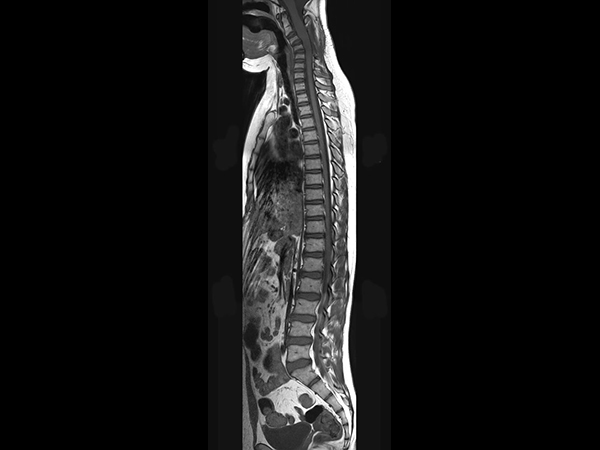

Sagittal T2w TSE (T-Spine)